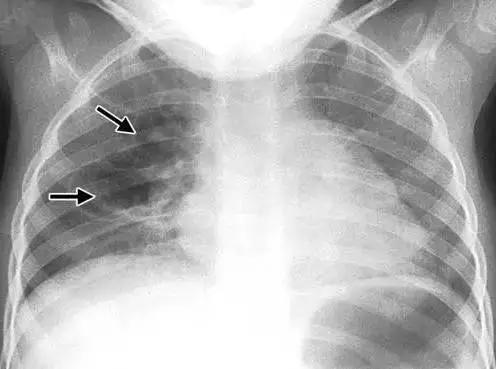

肺气囊、肺囊肿和肺大疱是三种常见的肺部疾病,它们虽然名称相似,但实际上是不同的病理状态。了解这三种疾病的区别,对于正确诊断和治疗至关重要。

肺气囊(pulmonary bulla)是一种肺部疾病,其特征是肺泡腔内压力升高,导致肺泡壁破裂并相互融合,形成含气囊腔。肺大疱(pulmonary emphysema)则是肺气肿的一种表现形式,主要由长期吸烟或暴露于有害物质引起,导致肺泡壁受损并破裂,形成较大的气隙。相比之下,肺囊肿(pulmonary cyst)是一种先天性或获得性的肺部囊性病变,其壁厚通常不超过4毫米。

这三种疾病的原因和症状也各不相同。肺气囊和肺大疱通常继发于小支气管的炎性病变,如哮喘、肺炎、肺结核等。肺囊肿则可能与肺的发育不良有关,也可能由感染、肿瘤等因素引起。症状方面,较小的肺气囊和肺囊肿可能无明显症状,而较大的肺大疱和肺囊肿可能导致胸闷、气短等症状。肺大疱还可能引起自发性气胸,表现为急性胸痛和呼吸困难。